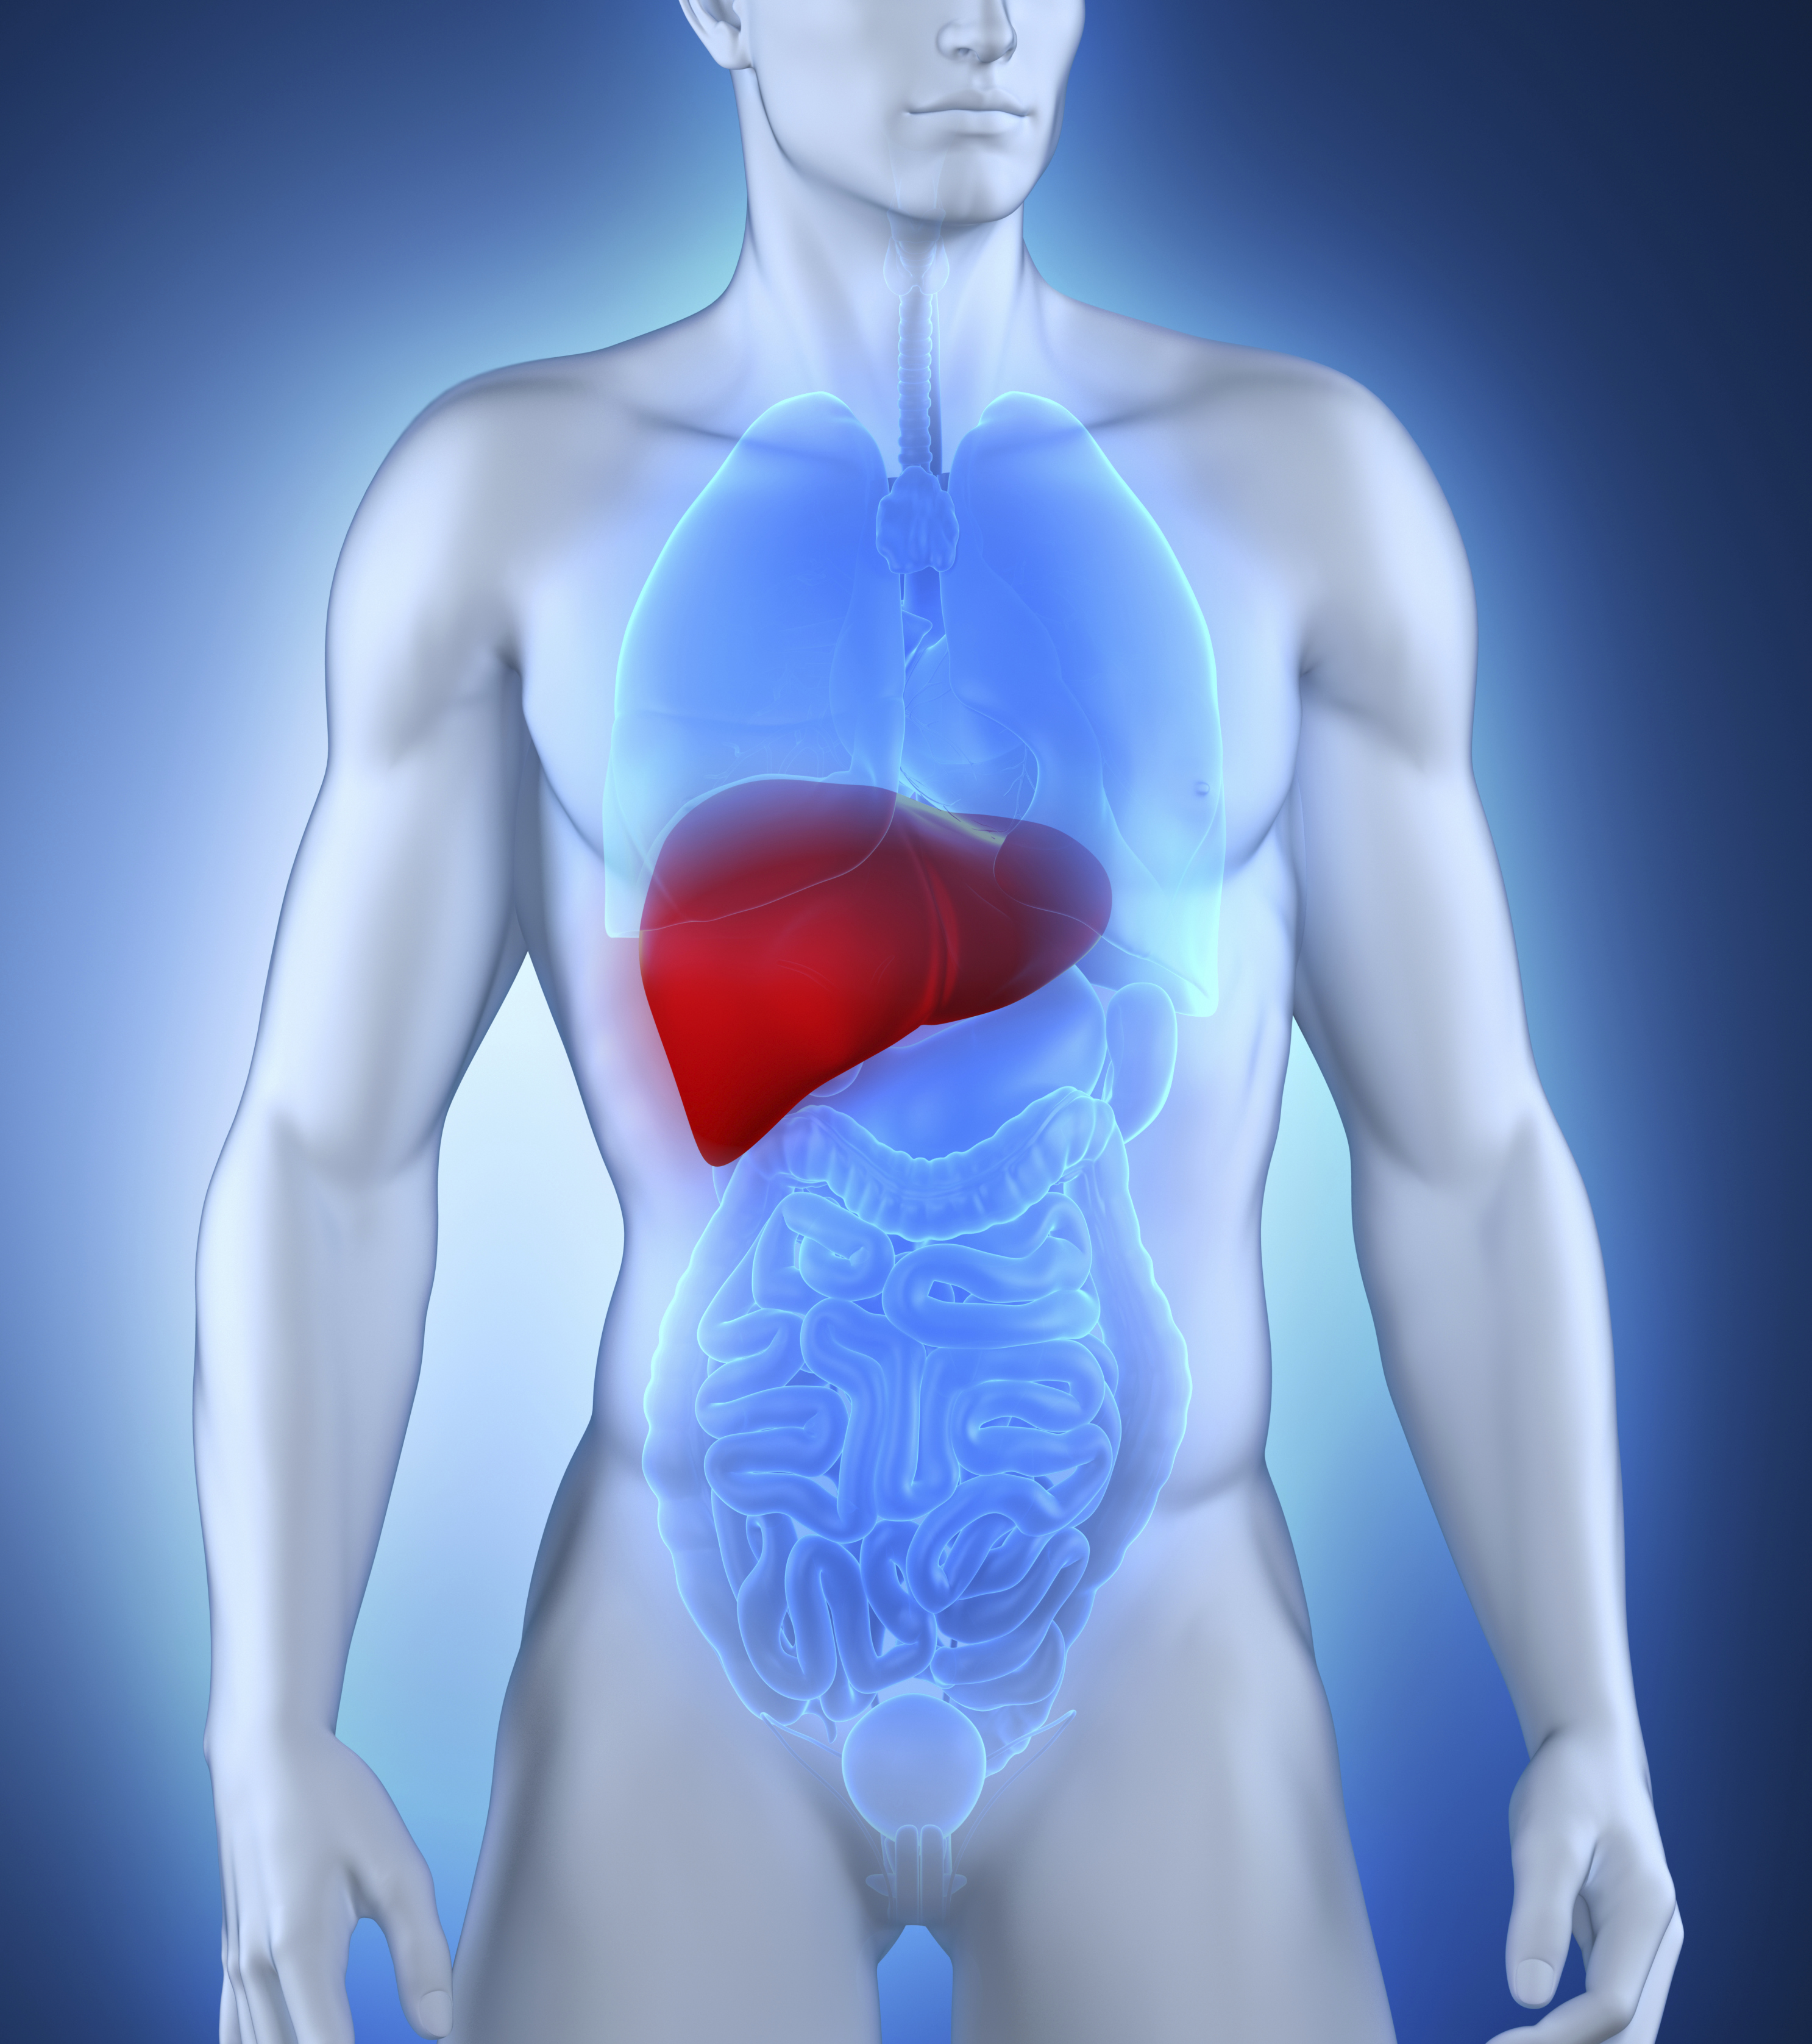

Le foie est le plus gros organe du corps humain, mais pèse à peine plus d’un kg. Il est le seul organe capable de se régénérer, mais sa bonne santé